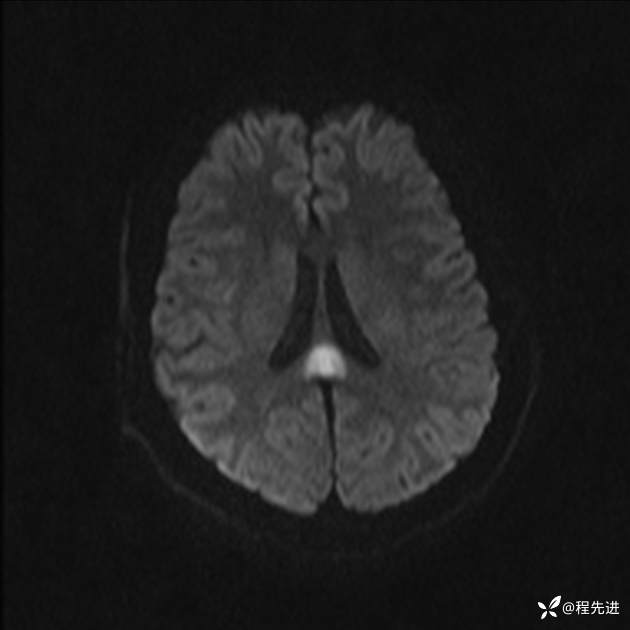

【患者信息】:女,25岁

【现病史及既往史】:言语含糊、意识状态改变1天。有下段剖宫产术10天病史。